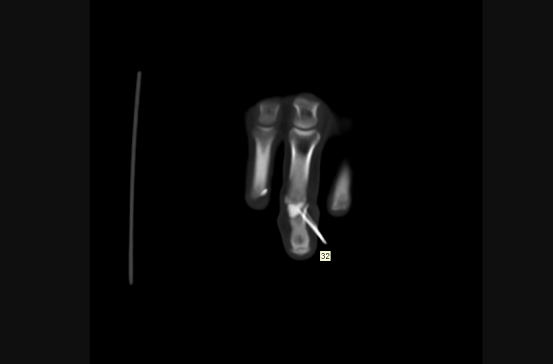

目前患者恢复良好,一段时间后,移植的关节便可和原本的关节完全一样,没有结构和功能差异。

术后手指关节恢复良好